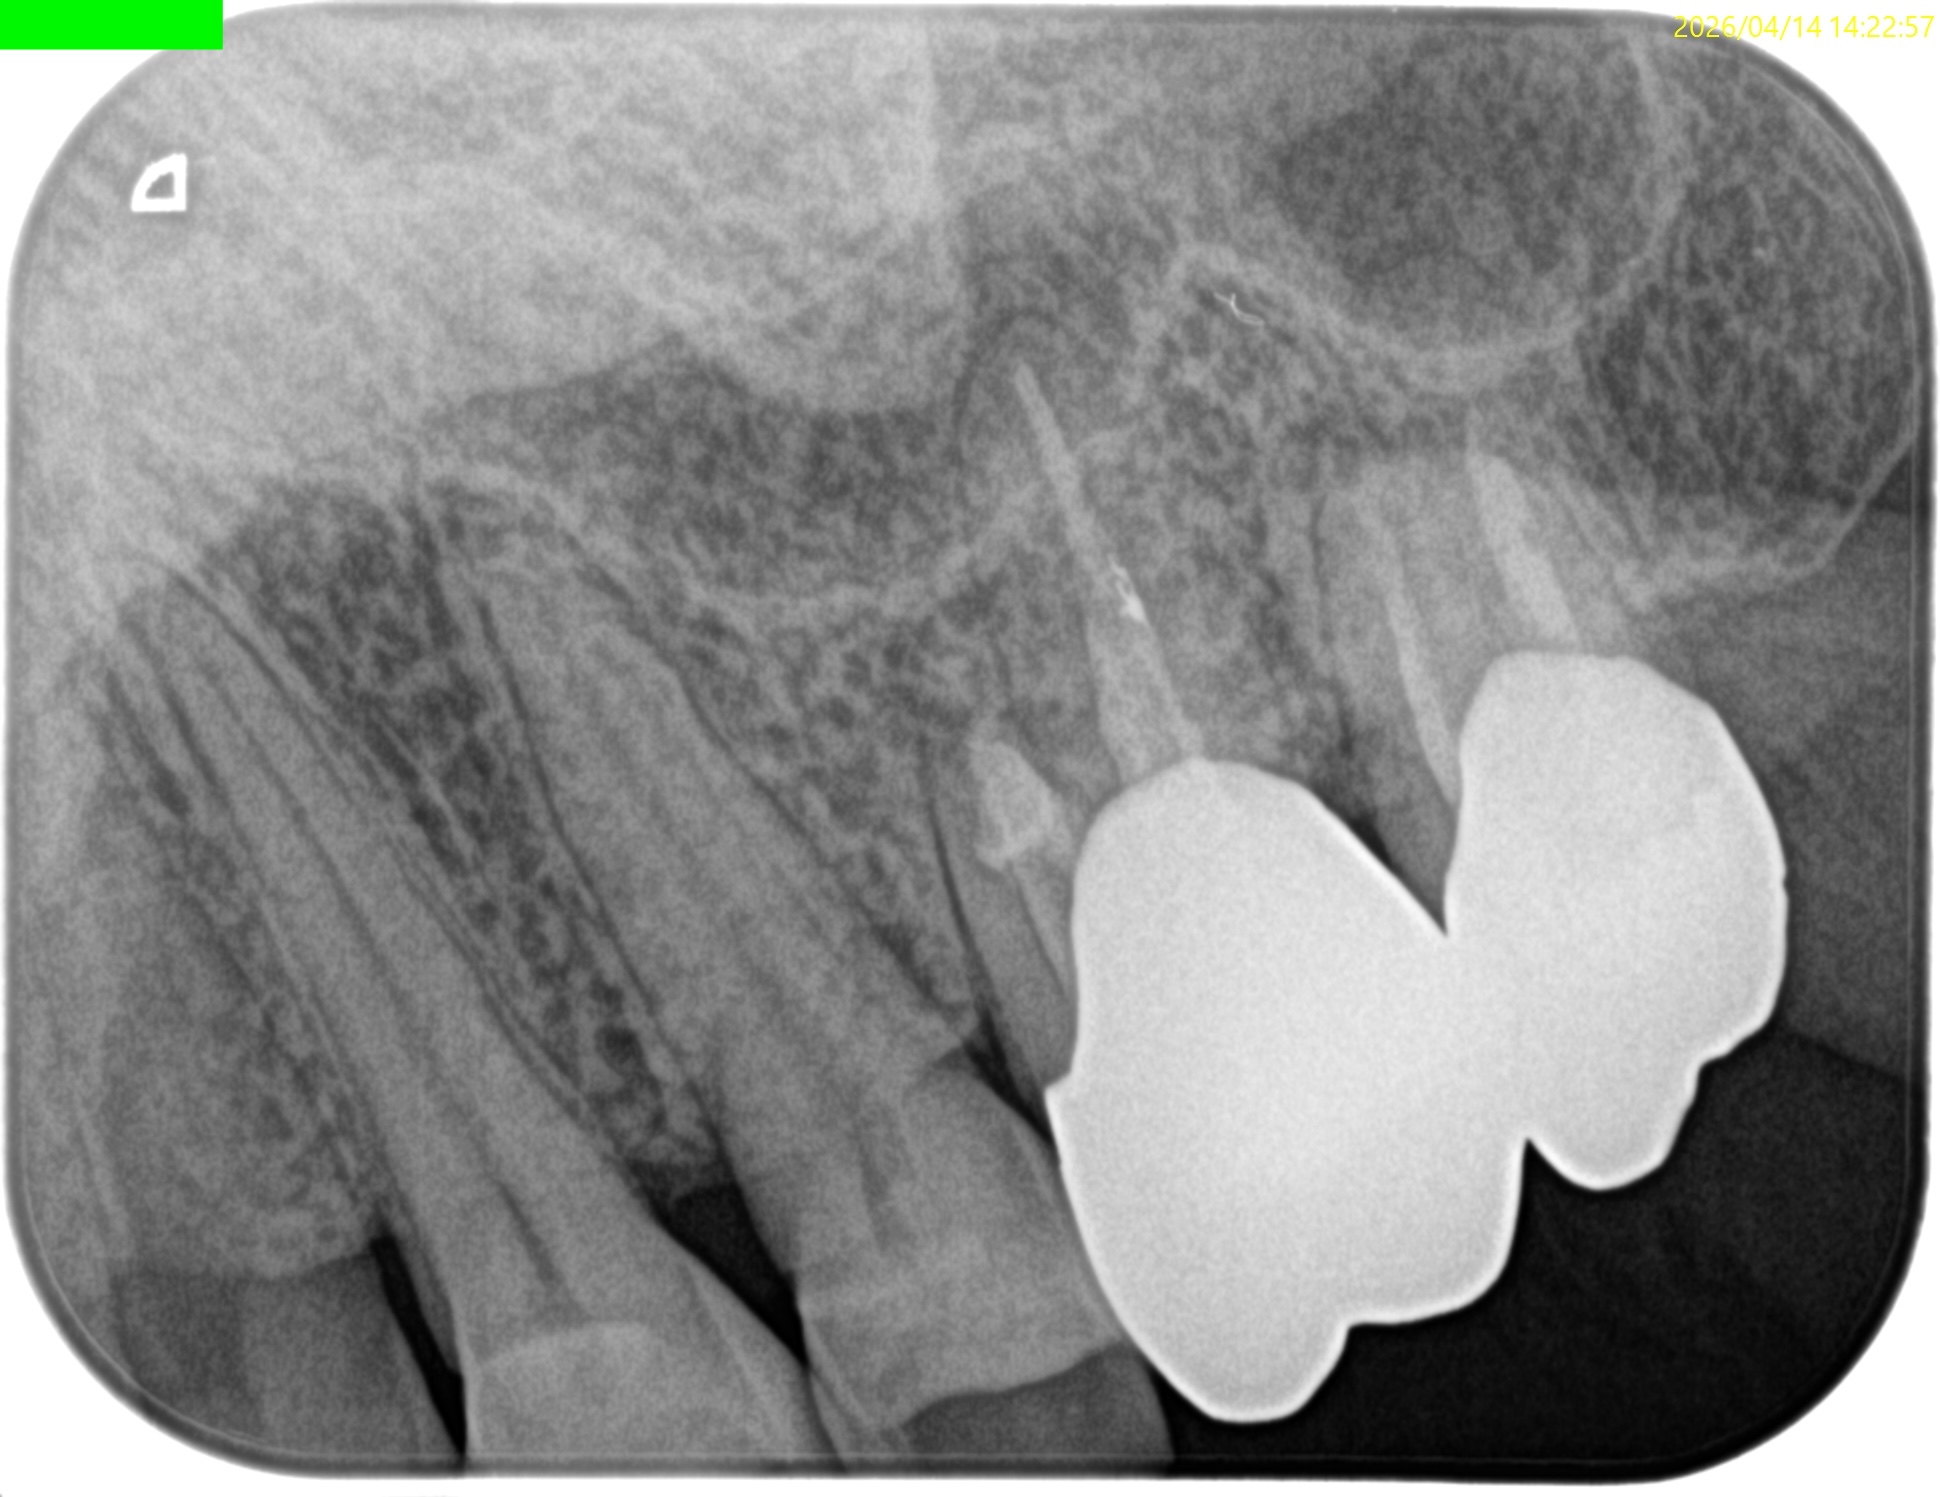

Retroprepで穿孔させてしまい、即日Retrofill(穿孔封鎖)した#14は治癒しただろうか?

1年前と比較した。

臨床症状、骨欠損も完治したのでこの日で終診とさせていただいた。